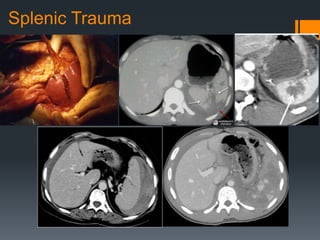

Splenic Trauma